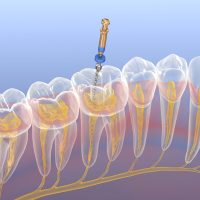

Gyökérkezelés